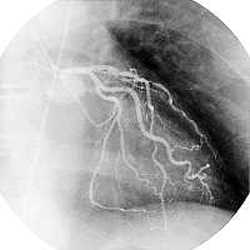

| 5.1. ARTÈRES |

Il existe 2 artères coronaires ainsi nommées car elle entoure le cœur comme une couronne au niveau du sillon atrio-ventriculaire.

5.1.1. ARTÈRE CORONAIRE GAUCHE

La coronaire gauche, en général plus volumineuse, naît plus haut que la coronaire droite.

Son diamètre est 4 à 5 mm.

Elle s'insinue entre l'auricule gauche et le flanc gauche de l'artère pulmonaire. Cette artère et ses collatérales cheminent le plus souvent dans les sillons du cœur, en grande partie masquées par des bandes graisseuses. Elle sont sinueuses pour s'adapter au changement de volume du cœur.

A la partie supérieure du sillon inter-ventriculaire antérieur.

La coronaire gauche et la coronaire droite sont des artères terminales. On pense qu'il existe quelques anastomoses entre les 2 artères coronaires mais qu'elles ne sont pas fonctionnelles. D'où les infarctus du myocarde.

5.1.2. ARTÈRE CORONAIRE DROITE

Son calibre est inférieur à celui de la coronaire gauche. Elle mesure 3,5 à 4 mm de diamètre.

Elle s'insinue sous l'auricule droit et gagne le sillon atrio-ventriculaire antérieur droit, dissimulée par des bandes graisseuses, contourne le bord du cœur et suit le sillon atrio-ventriculaire postérieur (ou sillon coronaire).

Comme pour la coronaire gauche, son trajet est très sinueux.

Au niveau de la "croix des sillons".

Comme la coronaire gauche, la coronaire droite est une artère terminale.

Coronaire gauche Coronaire droite